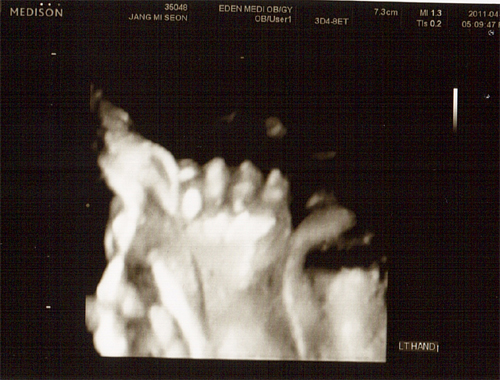

26주 4월 8일(금) 입체 초음파사진